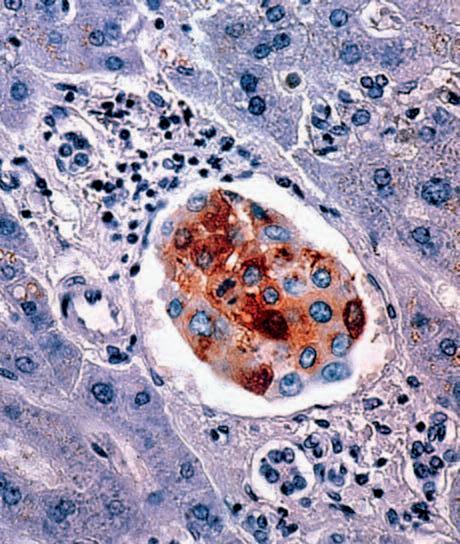

La pagina a fianco mostra l'immagine di una cellula tumorale reale, visualizzata al microscopio elettronico, che ingrandisce questa cellula 6500 volte rispetto alle sue normali dimensioni. Questo tipo di cellula prende il nome di carcinoma, cioè derivante da cellule epiteliali, il tipo di cellule che rivestono sia le superfici interne (polmoni, intestini) che esterne (pelle) del corpo.

Grazie a questo ingrandimento si possono identificare chiaramente alcune delle caratteristiche di tutte le cellule tumorali: a) l'enorme nucleo cellulare dalla forma insolita che spiega la loro grande capacità di riprodursi e b) la struttura non uniforme, complessa della superficie cellulare, che riflette una forte attività di secrezione di sostanze prodotte dalle cellule tumorali.

Una delle più importanti molecole secrete dalle cellule tumorali in grandi quantità sono gli enzimi a ‘forbice’ che digeriscono il collagene. Sono aggiunti graficamente a questa immagine, sotto forma di strutture simili ad un ‘pacman’ rosso.

Immagine al microscopio di cellule leucemiche. Le sfere rosse del pacmen rappresentano gli enzimi collagenasi.

La foto nella pagina a fianco mostra una sezione trasversale al microscopio del fegato di un paziente con ‘leucemia linfatica’. Ciascuno dei piccoli puntini viola nella foto è un globulo bianco (in questo caso linfocita) che ha invaso il tessuto del fegato (aree rosa).

Considerando l’enorme quantità di questi puntini viola e il numero di enzimi che assimilano il collagene che ciascuno produce, è facile prevedere l’ingente distruzione del tessuto connettivo e il danno apportato all’organo da questo tipo di cancro.

Immagine al microscopio della leucemia linfatica

Globuli bianchi affetti di cancro (linfociti) invadono il fegato L’enorme quantità di collagenasi prodotte da queste cellule distruggono l’organo e causano insufficienza epatica.

La foto nella pagina a fianco mostra una cellula cancerogena ad un microscopio.

Il corpo di questa cellula tumorale in migrazione si espande nella direzione del suo movimento all’interno del tessuto. Può formare una struttura ‘tentacolare’ che trascina la cellula tumorale lungo la superficie, in questo caso, di un vaso sanguigno.

Gli enzimi che digeriscono il collagene sono aggiunti per illustrare il processo mediante il quale qualsiasi ostacolo sul cammino di questa cellula tumorale viene superato.

Immagine al microscopio di cellule tumorali del seno (la massa di cellule marroni al centro) che nel fegato (struttura blu nello sfondo) formano una metastasi.